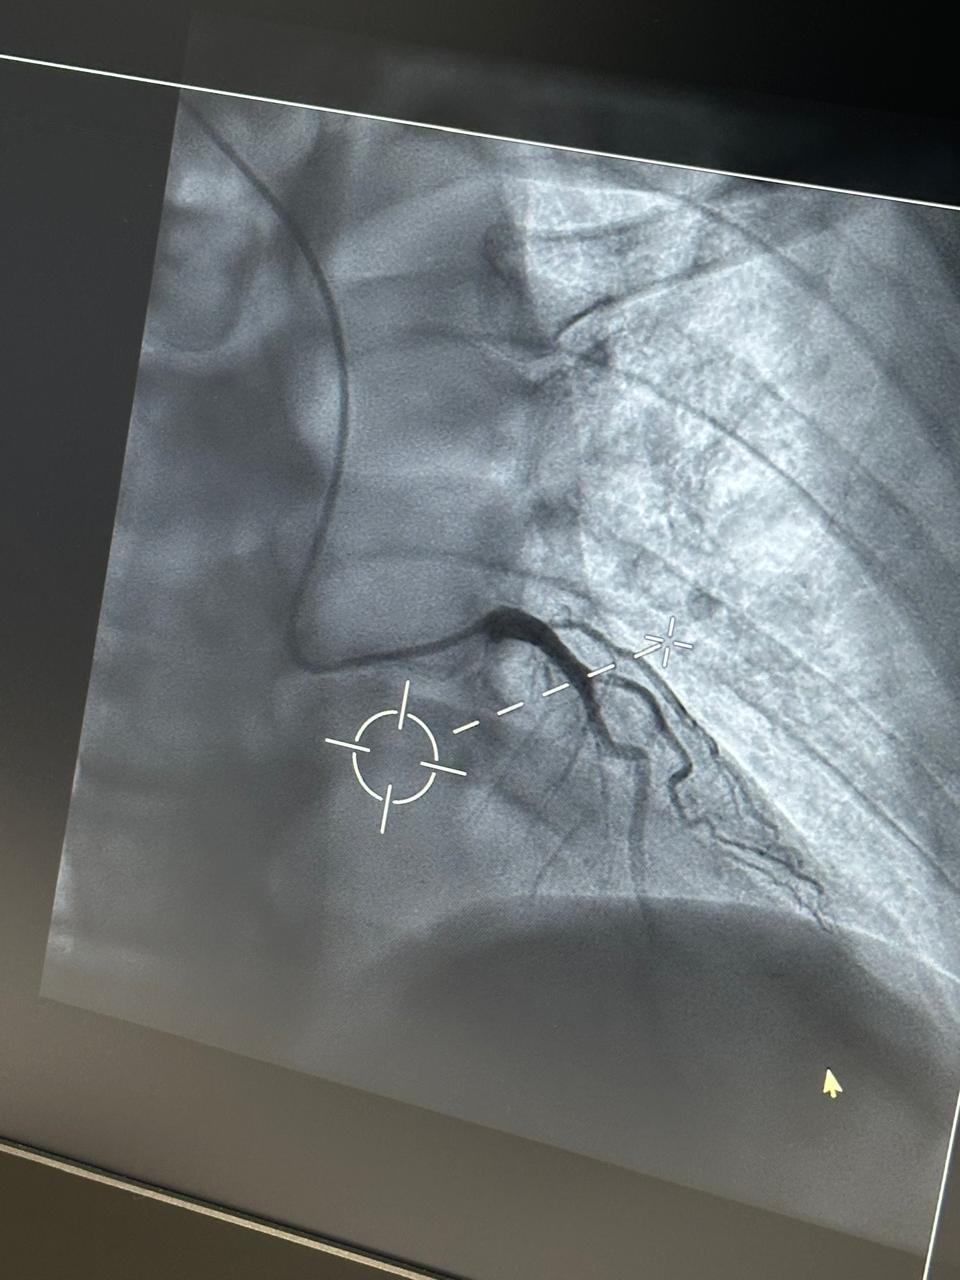

Sot u realizua me sukses koronarografia e parë pranë Spitalit Katolik Zoja e Këshillit të Mirë, duke shënuar kështu fillimin e një shërbimi të rëndësishëm për spitalin tonë.

Salla e re moderne e angiografisë me pajisjet më të avancuara garanton precizion të plotë diagnostik dhe cilësi të shkëlqyer të trajtimit për pacientët tanë sipas standardeve evropiane.

- Procedura e koronarografisë diagnostike u realizua me sukses nga ekipi ynë profesionist: Dr. Aurel Demiraj, Dr.Alk Shehu, Dr. Ervin Bejko dhe ekipi i infermierëve.